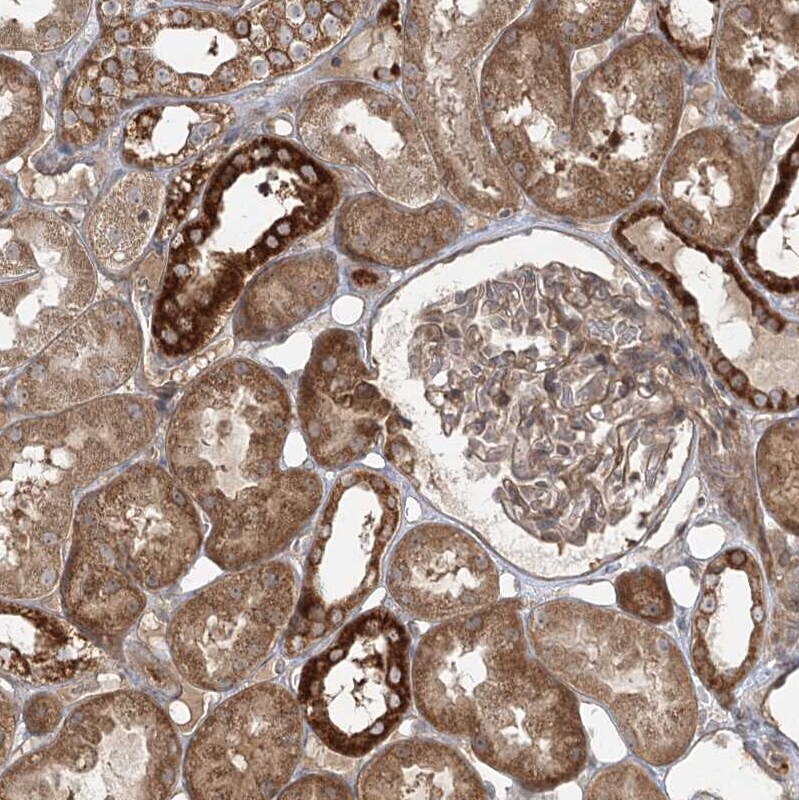

Supportive validation

- Submitted by

- Invitrogen Antibodies (provider)

- Main image

- Experimental details

- Immunohistochemical analysis of C5orf42 in human Kidney using C5orf42 Polyclonal Antibody (Product # PA5-57811) shows strong membranous and cytoplasmic positivity in cells in tubules and glomeruli.